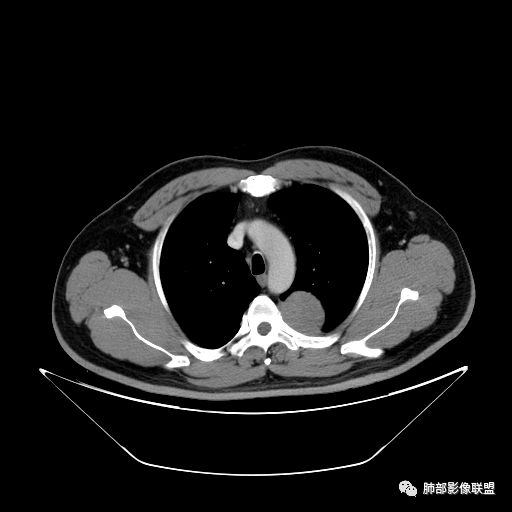

曹志勇:右肺尖后段类圆形病灶,边界清边,缘锐利,宽基底与胸膜相连,环形强化,内似见蛇纹血管征,考虑胸膜孤立性纤维瘤,右肺外底段病灶,考虑炎性可能大

崔刚:左侧胸膜外病变,胸膜掀起,考虑神经鞘瘤。

赵:左后纵隔神经鞘瘤,神经节节瘤待除外

红日东升:左侧胸椎旁肿块,边缘清晰光整,冠状位见D字征,未见支气管进入,肺组织受压表现,定位肺外。轻度强化,密度稍不均匀,临近肋骨变细,未见肺动脉供血,考虑良性肿瘤,神经源性可能。右肺下叶病灶,轻度强化,血管显影,边缘平直、凹陷,考虑炎性病变。

左肺下叶脊柱旁病灶,可见胸膜尾征,均匀强化,临近椎间孔未见扩大,考虑孤立纤维瘤,鉴别诊断神经源性肿瘤,右肺下叶病灶边缘平直,明显均匀强化,边缘清楚,考虑机化性肺炎。

张帅:患者中年男性,咳嗽 咳痰3月,痰为白色粘痰,左上肺病灶,边缘光滑,周围未见毛刺 分叶,肺组织受挤压,与胸膜关系密切,部分层面与胸膜脂肪间隙消失,有胸膜尾征,病灶定位于胸膜,病灶增强可见强化,边缘可见增强血管,内可见低密度区,考虑 孤立胸膜纤维瘤?神经鞘瘤?右肺下叶外基底段病灶,病灶与胸膜有牵拉,病灶边缘光滑,平直 u型征,未见明显毛刺,增强病灶内可见增强血管影,边缘低密度,考虑病灶内存在痰栓。右下肺病灶考虑良性炎症性病灶,ABPA?

张立:左侧胸椎旁肿块,边缘清晰光整,冠状位见D字征,未见支气管进入,肺组织受压表现,定位肺外。轻度强化,密度稍不均匀,,未见肺动脉供血,神经源性肿瘤,节细胞神经瘤可能。右肺下叶病灶,轻度强化,血管显影,边缘平直、凹陷,TB可能。

可芸:定位:肺外病变,胸椎旁肿块,边缘清晰光整,可见胸膜尾征无支气管进入,肺组织受压。轻度强化,密度稍不均匀,未见肺动脉供血,考虑良性肿瘤,神经源性,孤立性纤维瘤?右肺下叶病灶,轻度强化,血管显影,边缘平直、凹陷,炎性病变。

王秀仙:左侧后纵膈占位,位于胸膜下,胸膜被顶起,有胸膜尾征,密度均匀,轻度强化,内可见斑点钙化。周围肺组织结构推移。右肺下叶可见片状影,沿支气管走行,边缘平直收缩,强化明显,胸膜有牵拉。二元论,考虑1左侧后纵膈神经鞘瘤。鉴别SFT.2右肺下叶炎性肉芽肿。

心灵鸡汤:先定位再定性,左侧胸椎旁沟见一团状软组织影,边清,密度均,推挤周围组织,增强轻度强化,考虑为良性肿瘤,来源于后纵隔神经源性的肿瘤,神经鞘瘤可能,鉴别孤立性纤维瘤,孤立性真菌类。左肺下叶外基底段斑片影,倾向机化性肺炎或慢性炎症可能。请老师指点

王江涛:左侧脊柱旁软组织肿块,边界清楚,肺外胸膜来源,肺组织受压,增强有强化,考虑SFT大于鞘瘤;右肺下叶斑片影,明显强化,考虑炎性病灶。

李志国:左侧椎旁团块,宽基底、胸膜掀起,定位肺外,增强轻度强化,有蛇纹血管征,考虑孤立性纤维瘤,鉴别神经源性肿瘤

等待戈多:左侧脊柱旁软组织肿块,边界清楚,肺外胸膜来源,肺组织受压,增强有强化,考虑SFT 鉴别神经源性肿瘤;右肺下叶斑片影,明显强化,边缘平直 考虑炎性病灶。

三生石上:左侧脊柱旁软组织肿块,边界清楚,考虑神经源性肿瘤

薏米:左下近脊柱旁可见一结节状密度增高影,肺外,边界清,边缘规整,无分叶,无毛刺,无棘突,宽基底与胸膜相连,不均匀轻度强化,考虑为良性病变,神经源性可能性大,为神经鞘瘤,鉴别孤立性神经纤维瘤,神经节瘤,右肺片装密度增高影,考虑为炎症可能性大

崇军:左侧胸椎旁肿块,边缘清晰光整,有胸膜尾征,冠状位为D字征,定位肺外。轻度强化,密度稍不均匀,似乎看到肋间动脉供血,未见肺动脉供血,考虑良性肿瘤,神经源性可能。右肺下叶病灶,轻度强化,血管显影,边缘平直、凹陷,层面太少,暂时考虑炎性病变。

食客:左侧脊柱旁肿块,边界清楚,肺外来源 考虑神经源性;右肺下叶病灶,考虑炎性病灶。

长沟流月去无声:中年男性,慢咳起病,左后纵隔可见一大占位,D字征,胸膜掀起,有胸膜尾征,附近肺组织受挤压,血管纹理纠集,瘤肺界面清晰,较均匀轻-中度强化,瘤肺表面可见线样不张之强化影,供血血管来源不易确定,冠状位似乎见一纵隔血管出入,综合考虑神经源性肿瘤:神经纤维瘤,神经鞘瘤?右下外斑片密度影,估计炎性,但本次手术应该未处理。

张秀兰:定位:肺外来源没问题表现,紧贴胸壁,胸膜尾征,点状钙化,密度均 匀,轻度强化考虑:神经源性肿瘤,鞘瘤首选,节细胞瘤待排鉴别:1单发胸膜间皮瘤,间皮瘤也有强化,程度比这个略甚,少见2孤立性纤维瘤,血供丰富,小的瘤体也有比较明显的强化,瘤体越大滋养血管越丰富,强化越甚。

ZK金:定位:左肺下叶后综合脊柱旁肺外肿块,胸膜尾征,D字征,瘤肺交界面清晰,肺组织受压。影像表现:边界清晰,密度均匀,上下经线略横经。首先考虑神经源性肿瘤,神经节细胞瘤首选,鞘瘤和孤立性纤维瘤鉴别诊断。右肺下叶考虑炎症。

Yiren  Sishui(厶水伊人):肺外肿瘤,考虑神经源性肿瘤,鞘瘤首选,SFT待鉴别

1.左上胸内脊柱旁半圆形肿块,质地坚实,密度比较均匀。

2.病灶周边见胸膜掀起,应当考虑胸壁或是纵隔来源,肺内病变不会如此。

3.降主动脉这一相对固定结构向前方推移,提示病灶相对坚实且有牢固附着点,不支持来自柔软的肺组织。

就如同在腹部,能将肾脏推移的包块,应该来自腹膜后。

4.可疑肋间动脉病供血,提示肿块来自后纵隔的可能性。

5.相邻椎间孔未见扩大,也未见块影延入椎管,易起自于神经根的鞘瘤似乎找不到相关支持点。

6.未提供矢状位骨窗图像,如在肋骨内下缘观察到压迹有助于肋间神经的鞘瘤的判断,这是因为二者之间密切的毗邻关系。

7.静脉期轻度强化,注意不是环形强化,亦未显示明确的“AB区”,神经鞘瘤与副节瘤亦未找到支持点。

综上,病灶定位胸壁或后纵隔,就发病率而言,神经源性可能性较大。